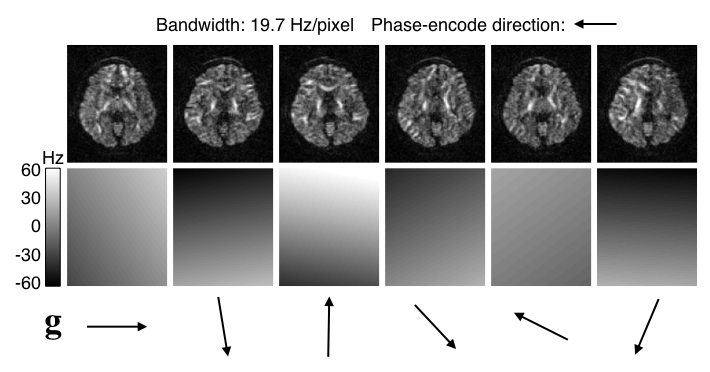

| Examples of EC-induced field and distorted images. |

|---|

|

| The top row shows six diffusion weighted images acquired with diffusion gradients along the direction indicated by the arrows below. Careful visual inspection shows that they are all distorted relative to each other. The off-resonance fields estimated by eddy are shown in the row below, scaled to -60--60 Hz. It can be seen that the estimated fields are to a first approximation a linear field along the direction of the diffusion gradient. |